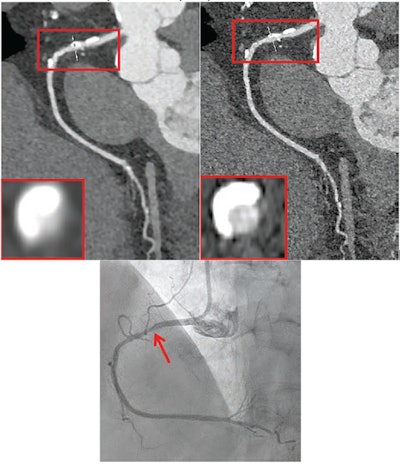

72-year-old female participant with heart failure. Patient underwent coronary CTA by photon-counting detector CTA, acquired in UHR mode. Agatston score was 1,615. Heart rate was 59 beats/min. (A) Reconstructed UHRnormal image. Proximal RCA shows calcified plaque. Inset shows cross-section of RCA at level of thin line traversing vessel. (B) Reconstructed UHRthin image. Proximal LCX shows calcified plaque. Inset shows cross-section of RCA at level of thin line traversing vessel. Insets show less blooming artifact from calcified plaque for UHRthin than for UHRnormal. Stenosis at site of calcification was measured as 60% for UHRnormal and 30% for UHRthin. (C) Image from subsequent invasive coronary angiography shows 30% stenosis of RCA (arrow). UHR = ultrahigh resolution. Images and caption courtesy of the AJR.72-year-old female participant with heart failure. Patient underwent coronary CTA by photon-counting detector CTA, acquired in UHR mode. Agatston score was 1,615. Heart rate was 59 beats/min. (A) Reconstructed UHRnormal image. Proximal RCA shows calcified plaque. Inset shows cross-section of RCA at level of thin line traversing vessel. (B) Reconstructed UHRthin image. Proximal LCX shows calcified plaque. Inset shows cross-section of RCA at level of thin line traversing vessel. Insets show less blooming artifact from calcified plaque for UHRthin than for UHRnormal. Stenosis at site of calcification was measured as 60% for UHRnormal and 30% for UHRthin. (C) Image from subsequent invasive coronary angiography shows 30% stenosis of RCA (arrow). UHR = ultrahigh resolution. Images and caption courtesy of the AJR.

The key finding of the work was that both standard resolution and ultrahigh resolution PCCT achieved high diagnostic performance for significant stenosis using ICA as the reference standard -- although the team did note that "the superior diagnostic performance of UHR mode was most evident in patients with heavily calcified vessels," writing that "radiology practices could consider prioritization of UHR mode for patients with known extensive coronary calcification or with strong clinical suspicion for severe CAD."